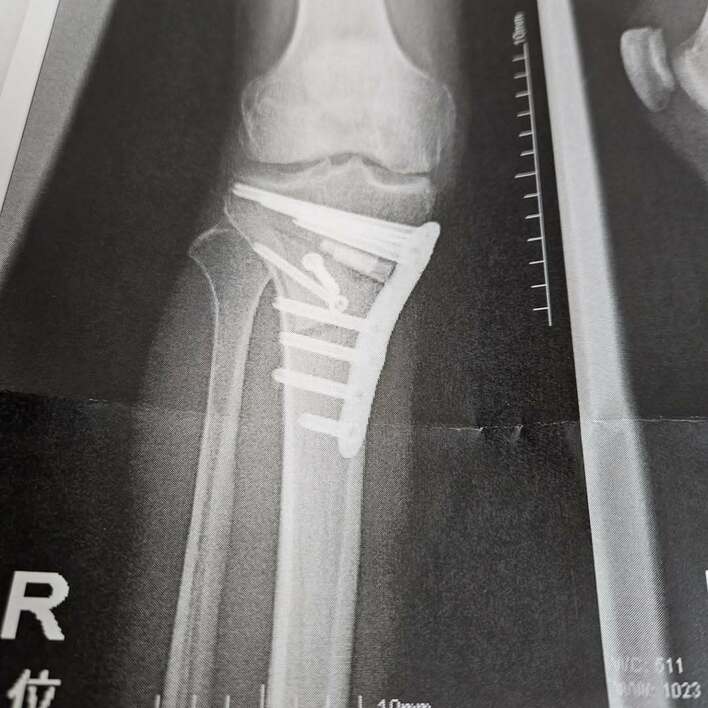

手術から約2週間後の4月30日には、「先生曰くめちゃくちゃ順調とのこと病院スタッフ様感謝しかありません」と、手術をした医師や病院スタッフの方々への感謝の気持ちをつづるとともに、膝のレントゲン写真を公開。

そこには、大きなボルトがくっきりと写っています。